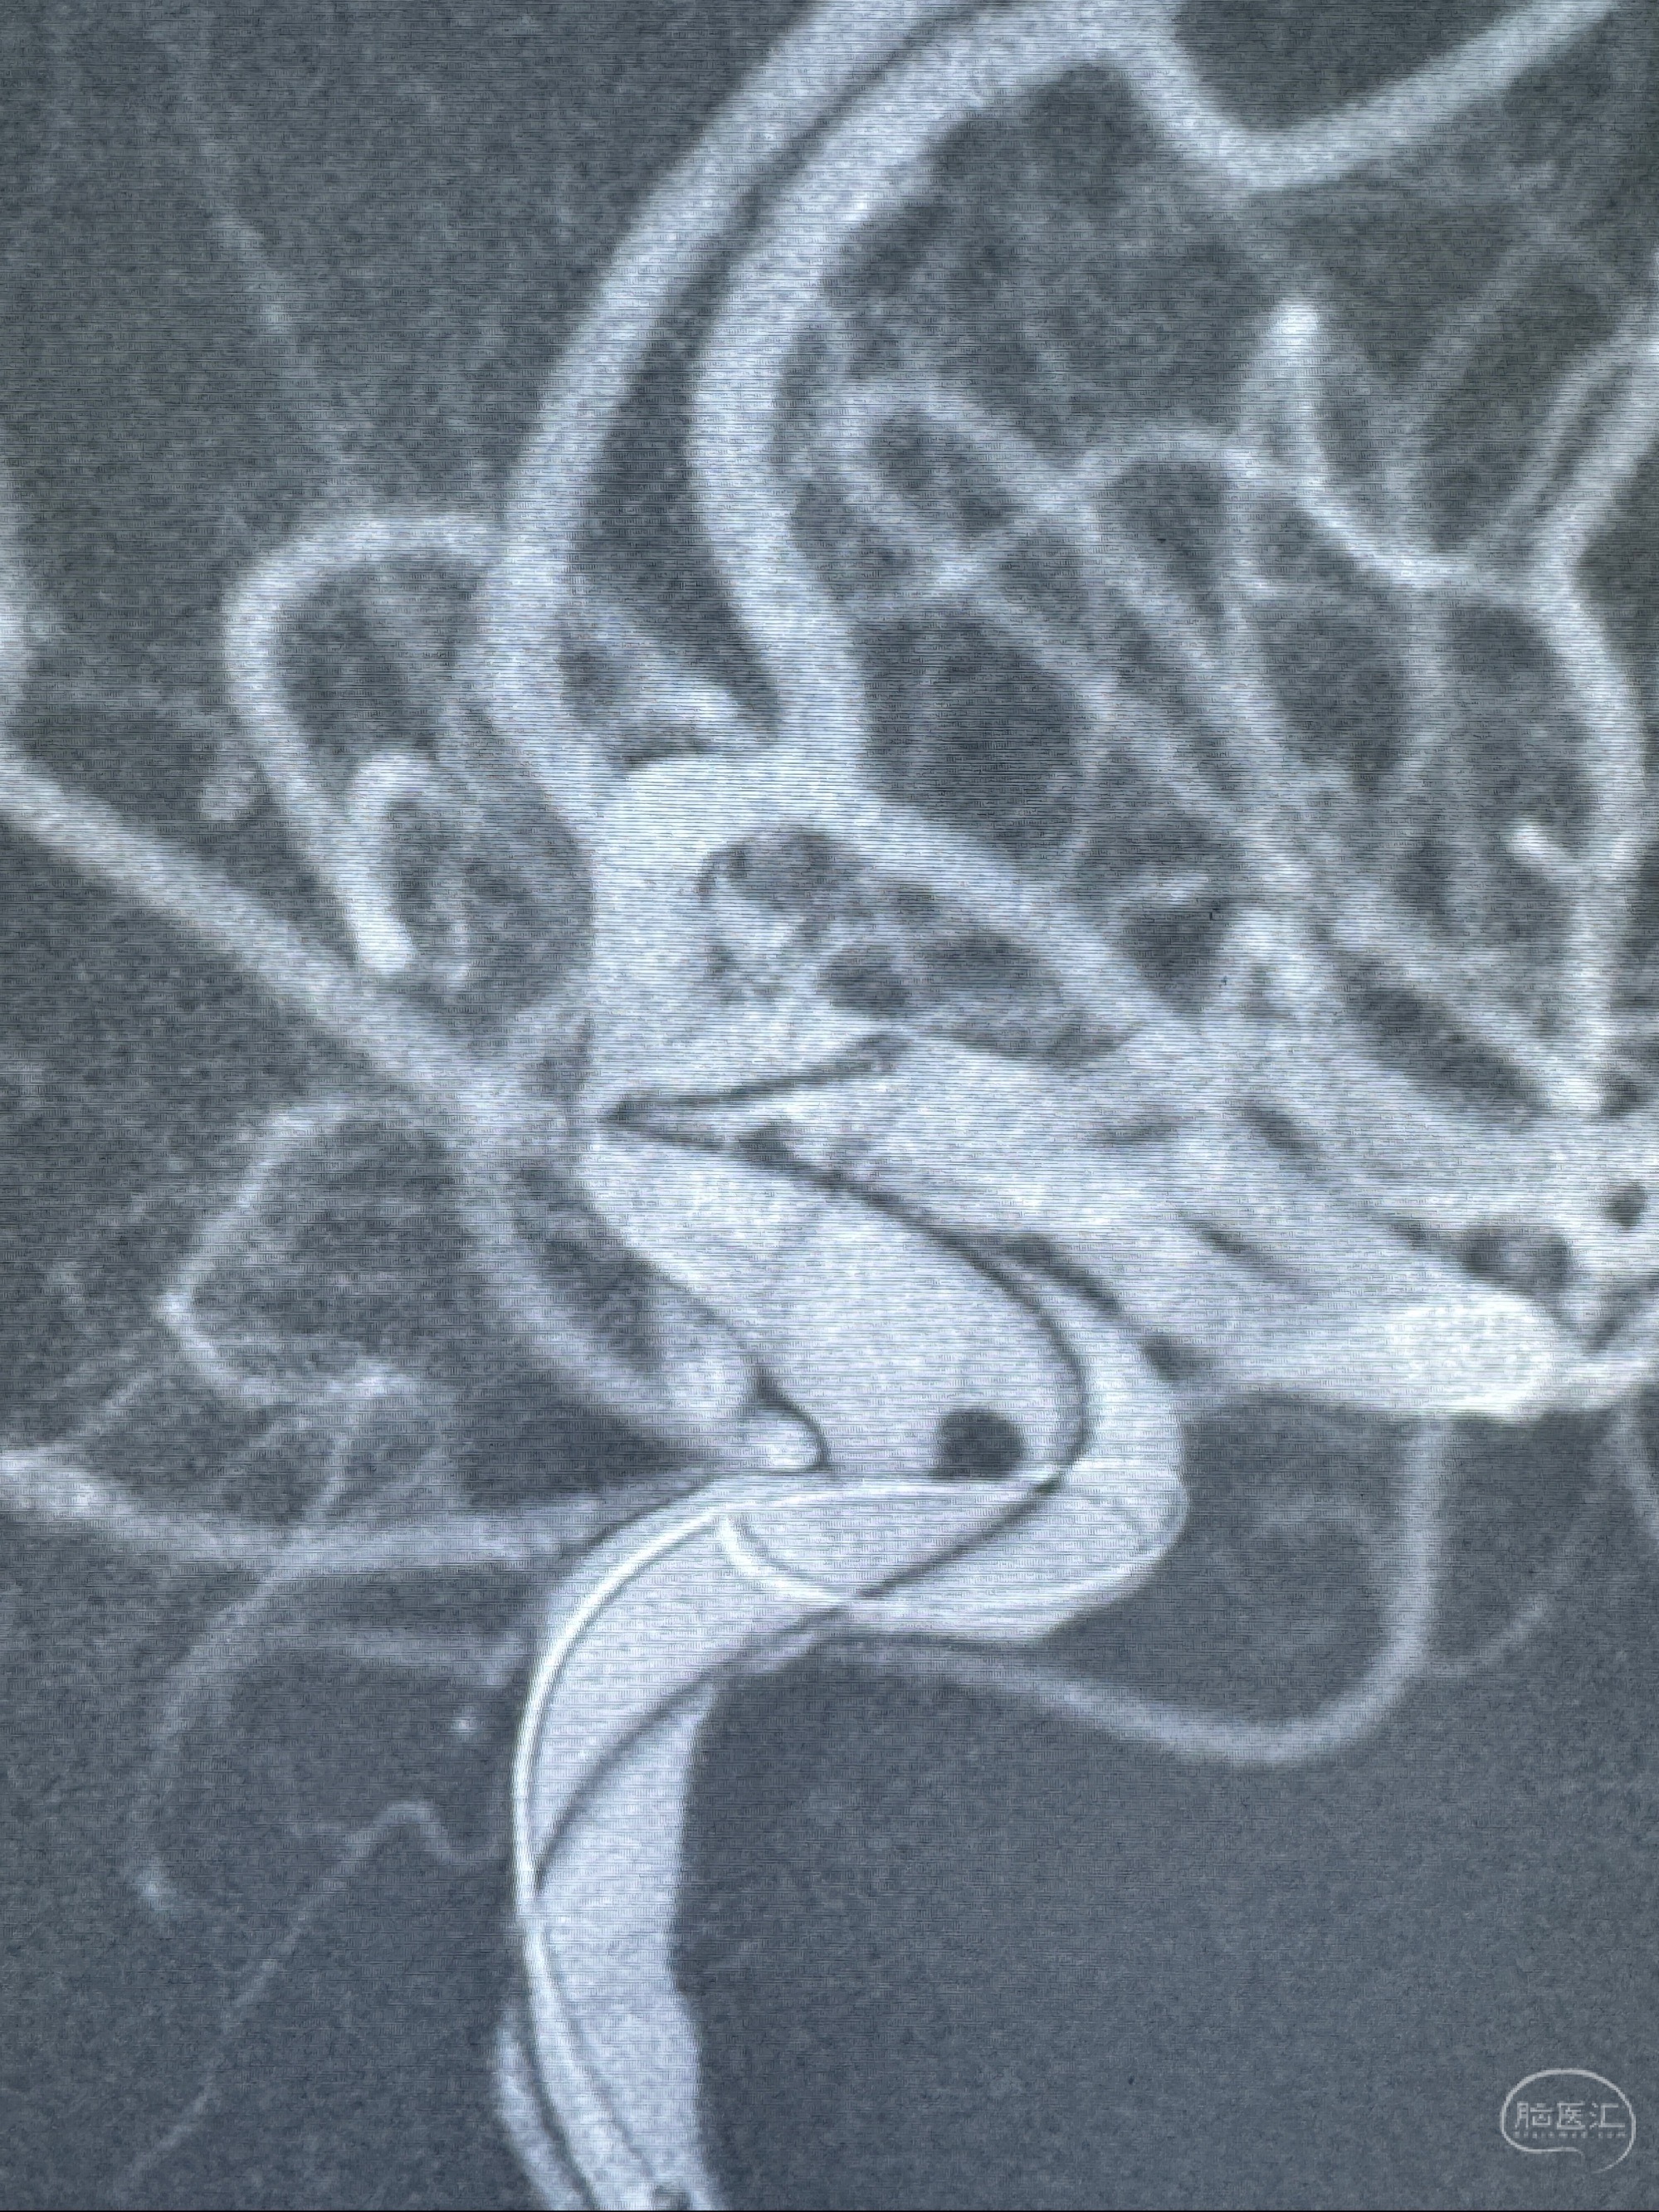

2023-11-13DSA:左侧颈内动脉眼动脉后壁动脉瘤

2023-11-29全麻下行NeuroformEZ4.5-20mm支架辅助栓塞